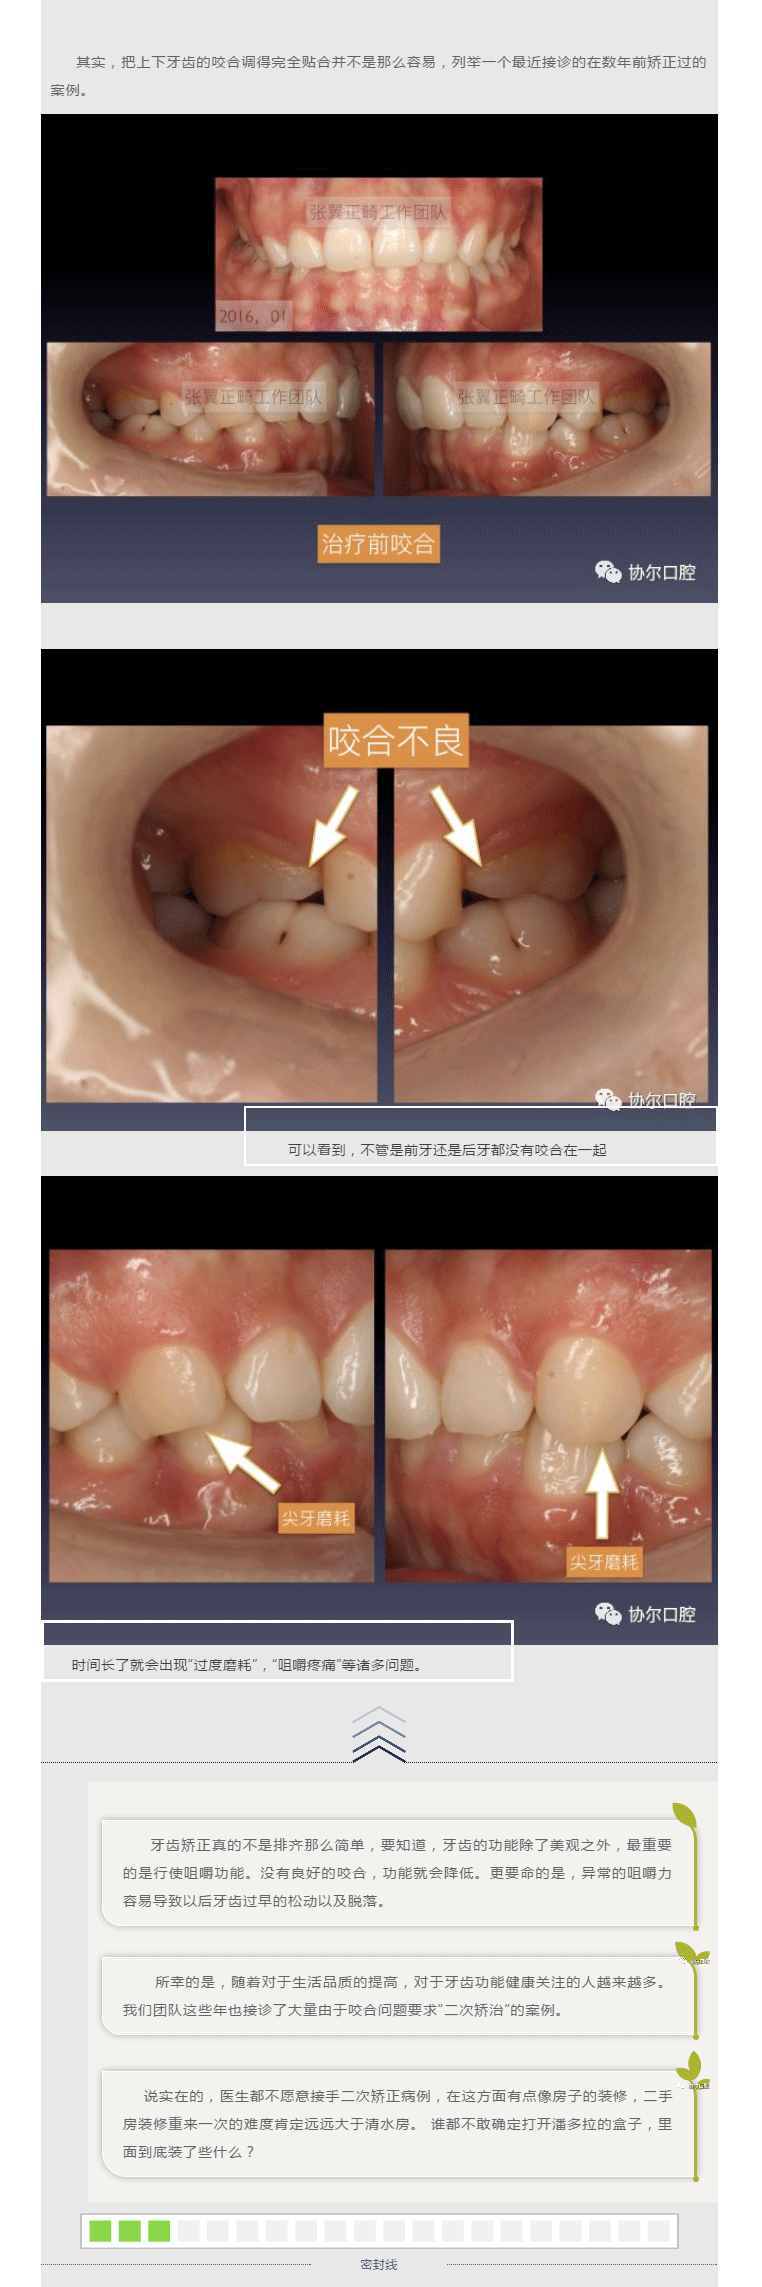

前牙内倾的二次矫正案例分享